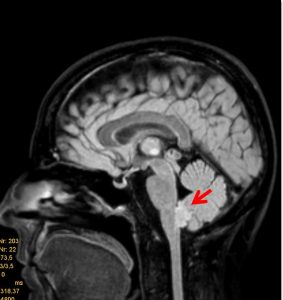

Τα επενδυμώματα ανήκουν στα γλοιώματα και αναπτύσσονται τυπικά εντός ή πλησίον του επενδύματος του κοιλιακού συστήματος του εγκεφάλου. Η πιο συνηθισμένη θέση είναι η περιοχή της παρεγκεφαλίδας (Εικόνα 1 & 2).